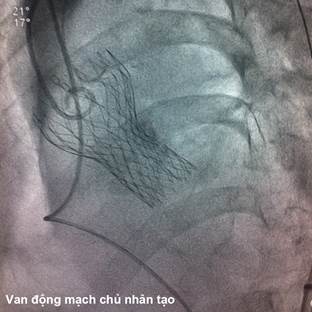

Dây dẫn Amplatz siêu cứng kích cỡ 0,035 inch (hãng Boston Scientific, Hoa Kỳ) được đẩy xuống buồng thất trái qua sheath 18 French. Tiến hành nong van động mạch chủ sử dụng bóng đường kính 22 mm, chiều dài 30 mm (hãng NuMED, Hoa Kỳ) khi tiến hành tạo nhịp thất nhanh. Sau đó, van sinh học CoreValve kích thước 29 mm được đặt ở vòng van động mạch chủ dưới hướng dẫn của màn huỳnh quang tăng sáng. Bệnh nhân xuất hiện bloc nhĩ thất độ 3 thoáng qua sau khi đặt van, tuy nhiên sau đó tự hồi phục về nhịp xoang. Kết quả chụp động mạch chủ cho thấy van động mạch chủ nhân tạo nằm đúng vị trí, chỉ có hở rất nhẹ cạnh chân van. Thông tim cho thấy không còn chênh áp qua van động mạch chủ (hình 3). Siêu âm tim qua thực quản và chụp gốc động mạch chủ ngay sau khi đặt van cho thấy van nằm đúng vị trí, hở rất nhẹ quanh van (hở độ I). Sau khi đã kiểm tra vị trí van trên phim chụp mạch cản quang và siêu âm tim, sheath 18 Fr được rút ra và động mạch đùi được đóng lại bằng 2 dụng cụ Perclose.

Hình 2: Van động mạch chủ CoreValve được đặt đúng vị trí